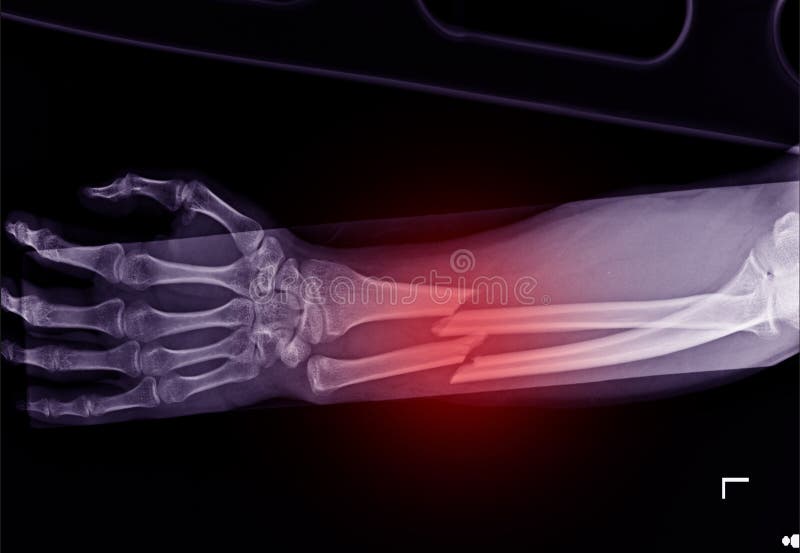

From www.dreamstime.com

Fracture Shaft Of Radius & Ulnar Bone Stock Photo Image of crash Radius Bone Hurts To Touch — if it’s injured, radial nerve pain usually occurs when your palm is pressed against something and your wrist is bent back. the most common symptom is pain in the forearm a couple of inches below the elbow. while there are many reasons for radial wrist pain, de quervain’s tenosynovitis is a common pathology and is described. Radius Bone Hurts To Touch.